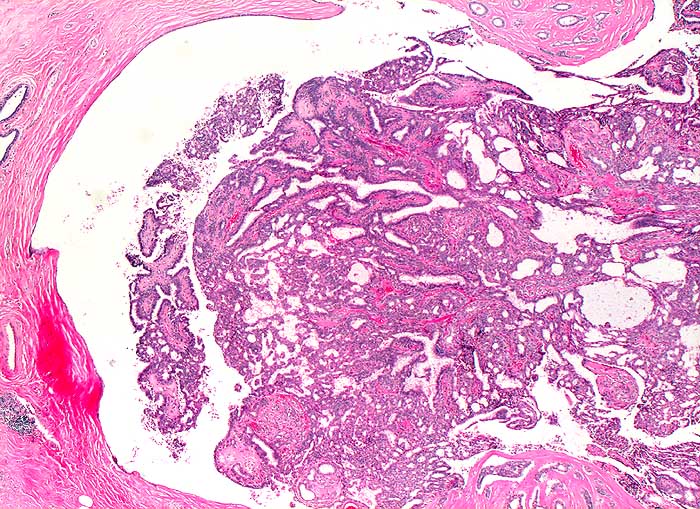

p/ Milchgangpapillom

Milchgangpapillom

Papilläre Zellverbände oder Zellballen auf zystischem Hintergrund sprechen für eine papilläre Neoplasie. Feinnadelpunktate von papillären Neoplasien sind oft blutig. Gutartige Papillome gleichen zytologisch Fibroadenomen. Geringere oder fehlende Stromakomponente, Zystenbildung, Zellballen, Einblutung und klinische Präsentation in Form einer einseitigen hämorrhagischer Mamillensekretion sprechen für ein Papillom. Sowohl benigne als auch maligne papilläre Neoplasien können ein relativ blandes uniformes Zellbild zeigen. Papilläre Karzinome erscheinen oft monomorpher als gutartige Papillome. Hohe Zellularität, zahlreiche Einzelzellen und die Abwesenheit benigner Zellen (apokrine Zellen, Myoepithelien) sprechen eher für ein papilläres Karzinom. Meist handelt es sich dabei um nicht invasive intraduktale Karzinome.